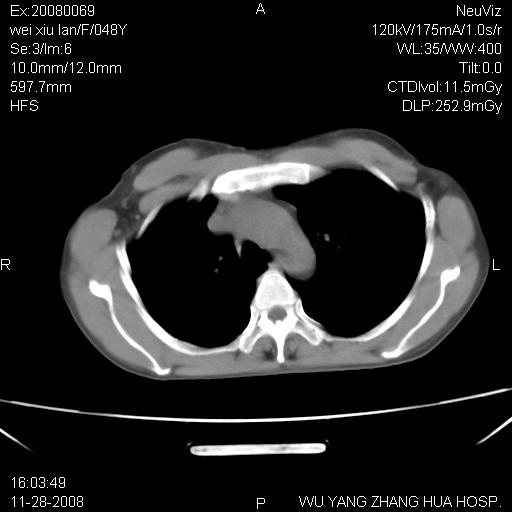

标题: CT16847:女,48岁,咳嗽,发热两日,平常偶有上腹部不适。 [打印本页]

标题: CT16847:女,48岁,咳嗽,发热两日,平常偶有上腹部不适。

能否考虑食管裂孔疝?请老师们多多指教。

这个是左侧膈膨升伴不完全性胃翻转,手术将松弛的左横膈膜折叠缝合即解决问题。

支持左侧膈疝,心脏受压右移.

胃、脾脏及部分肠管明显升高,并压迫心脏移位,

首先考虑:左侧膈疝。

左侧胸腔内见胃肠及脾脏影

支持膈疝

左膈顶及肋膈角均上移,膈面光滑,考虑左膈肌麻痹